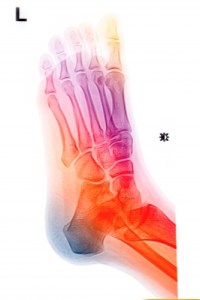

Each foot has 3 main arches: from the heel to the distal end of the first metatarsal (base of big toe), from the heel to the distal end of the fifth metatarsal (base of little toe) and the line connecting the distal ends of the first and fifth metatarsal. This creates a triangle of support for each foot. There is also a 4th arch which goes across the tarsal bones.

Image courtesy of Praisaeng at FreeDigitalPhotos.net